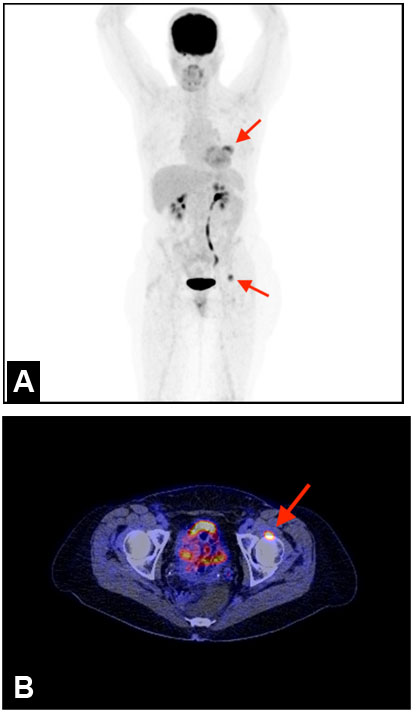

A 65-year-old woman had six-month of left buttock painless soft tissue mass. She underwent polypectomy for colon adenoma one year ago. On physical examination, a rubbery and movable mass in the buttock was palpable, which measured a size of 17 mm × 17 mm using vernier caliper. Coronal and axial MRI showed a mass in the subcutis of buttock and attached to the gluteal fascia that had homogeneous intermediate intensity on T1-weighted image (Figure 4A and Figure 4B). Corresponding axial T2-weighted image revealed a mass to be inhomogeneously high signal intensity (Figure 4C).

A percutaneous needle biopsy was performed under local anesthesia using 1% lidocaine. Histologically, the tumor is composed of spindle cells without nuclear atypia and abundant vessels with perivascular hyalinization (Figure 2D). Immunohistochemically, the tumor cells were negative for CD34, S100, SMA, and β-catenin. Mib-1 (Ki-67) index was less than 2%. The histological diagnosis was suggested AFST. At surgery, the tumor was resected with the cuff of surrounding fatty tissue and also with gluteal fascia since the bottom of tumor firmly attached to the underlying fascia. The definite diagnosis of AFST was made from surgical specimen. There was no recurrent tumor one year after the surgery.

Figure 4: Case 3. Angiofibroma of soft tissue in the buttock coronal (A) and axial (B) MRI shows a mass in the subcutis of buttock (black arrows) and attached to the gluteal fascia (white arrow) that had homogeneous intermediate intensity on T1-weighted image (TR/TE=476/9.90). Corresponding axial T2-weighted image (TR/TE=3110/105) reveals a mass to be inhomogeneously high signal intensity (C).